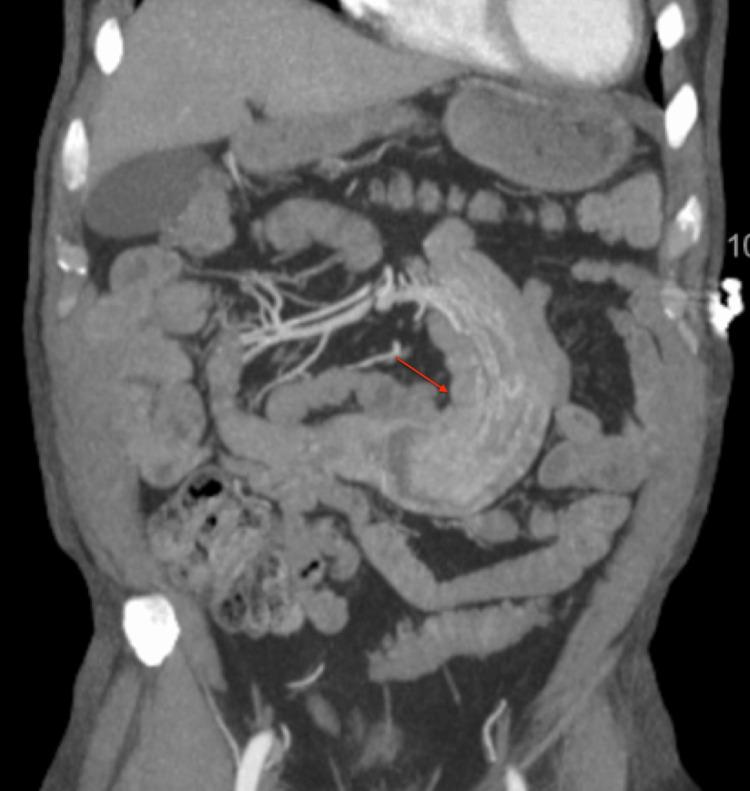

Renal cell carcinoma (RCC) most commonly metastasizes to the lungs, and it is uncommon for RCC to metastasize to the small bowel. Small bowel metastasis commonly presents with gastrointestinal (GI) bleeding. In rare cases, a metastatic small bowel mass can serve as a lead point for intussusception. In this report, we present the case of a male patient whose chief complaint was melena. The patient denied any abdominal pain or nausea. Investigation with push enteroscopy revealed a jejunal mass, and further evaluation with CT showed small bowel intussusception. The patient subsequently underwent small bowel resection and anastomosis. Histopathology confirmed that the jejunal mass was metastatic RCC. We present this case in order to showcase the utility of push enteroscopy in the diagnosis of small bowel metastasis in RCC.

摘要

肾细胞癌(RCC)最常转移至肺部,而RCC转移至小肠并不常见。小肠转移通常表现为胃肠道(GI)出血。在罕见情况下,转移性小肠肿块可作为肠套叠的起始点。在本报告中,我们介绍了一名以黑便为主诉的男性患者。患者否认有任何腹痛或恶心症状。推进式小肠镜检查发现空肠有肿块,CT进一步评估显示小肠套叠。该患者随后接受了小肠切除和吻合术。组织病理学证实空肠肿块为转移性RCC。我们展示此病例是为了说明推进式小肠镜在诊断RCC小肠转移中的作用。